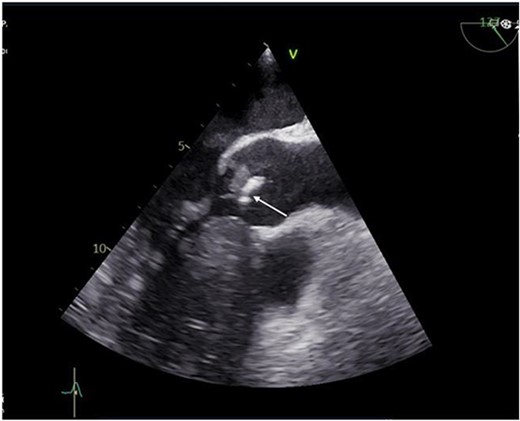

A 55-year-old gentleman presented to the emergency department with a 5-month history of ‘feeling unwell’, associated with weight loss, night sweats, cough, and lower limb weakness. He was treated as an outpatient for 3 weeks with antibiotics but had no respite and was eventually admitted to the hospital due to persistent symptoms. Transoesophageal echocardiography (TOE) showed a 10 mm vegetation prolapsing into the left ventricular outflow tract, attached to a bicuspid, calcified aortic valve, with severe aortic regurgitation (Fig. 1). He had an aortic valve area of 2.0cm [2] and left ventricular ejection fraction of 65%.

Preoperative transthoracic echocardiogram (TTE) showing vegetation on the aortic valve.